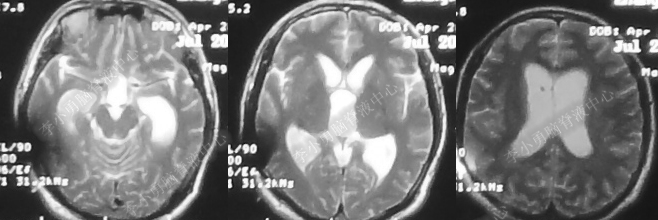

因头晕及视力下降等症状持续了3个月无好转,转至乌鲁木齐的新疆某三甲医院。住院后的2019年4月17日即发病后104天,查头颅核磁见脑室扩张程度较3个月前无明显变化(图-4)。

图-4:2019年4月17日头核磁